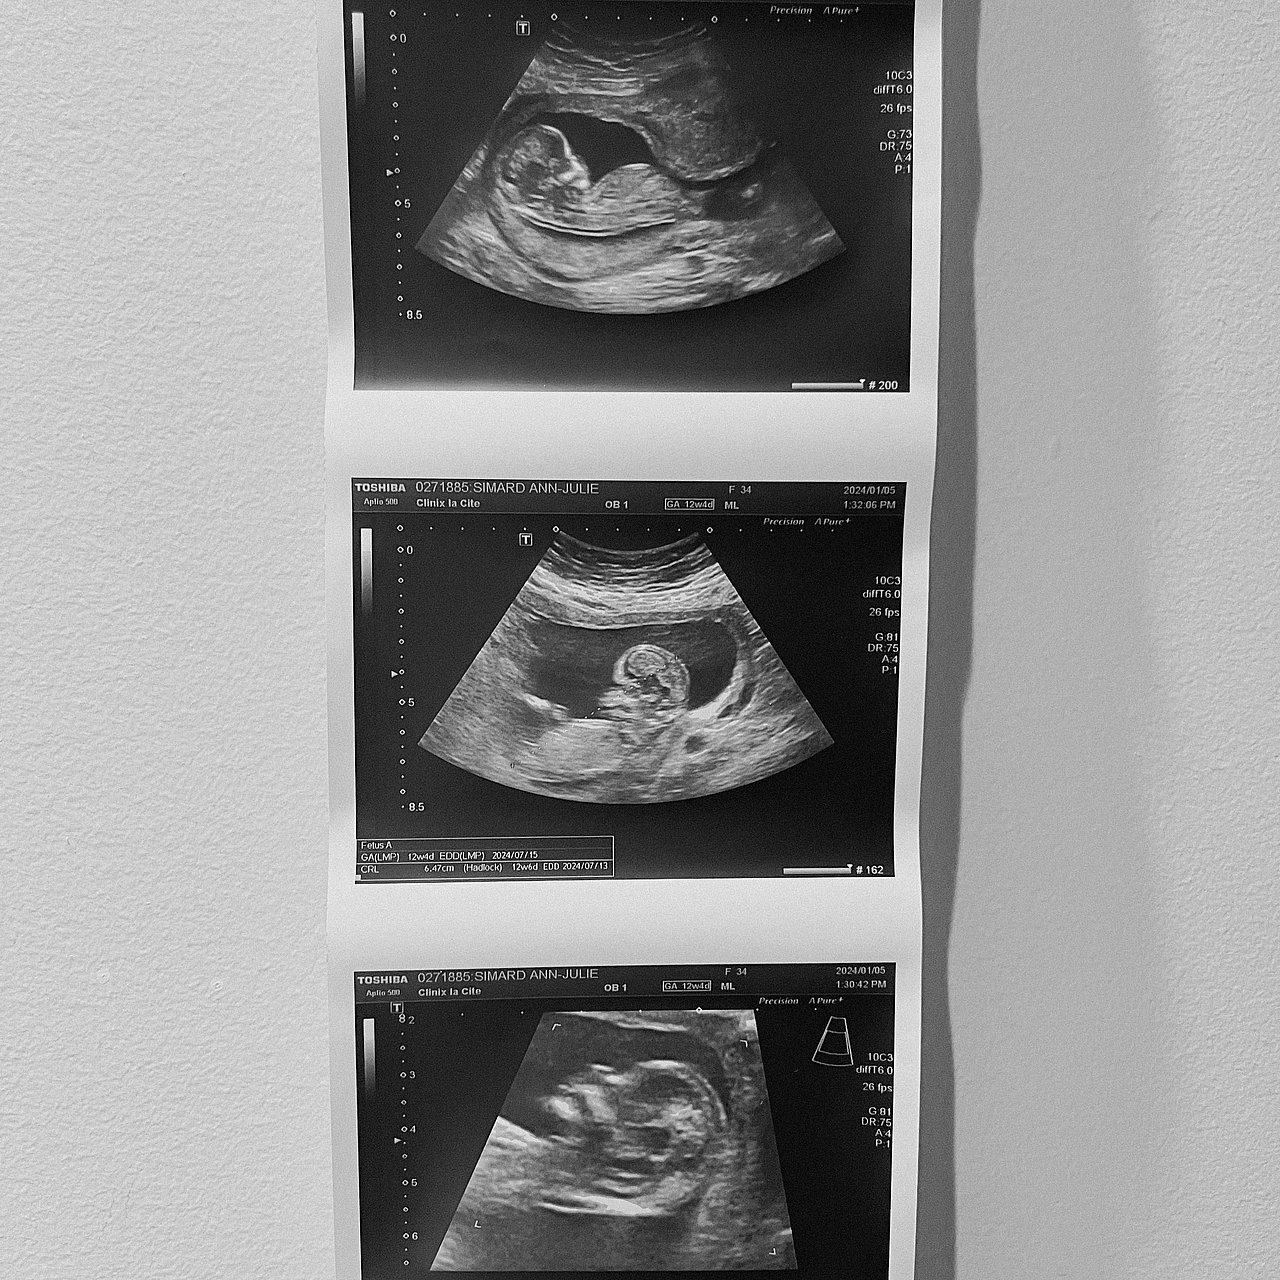

Première Échographie de Lucie

C‘est peut être les première image d’une petite Lucie ou un Laurent